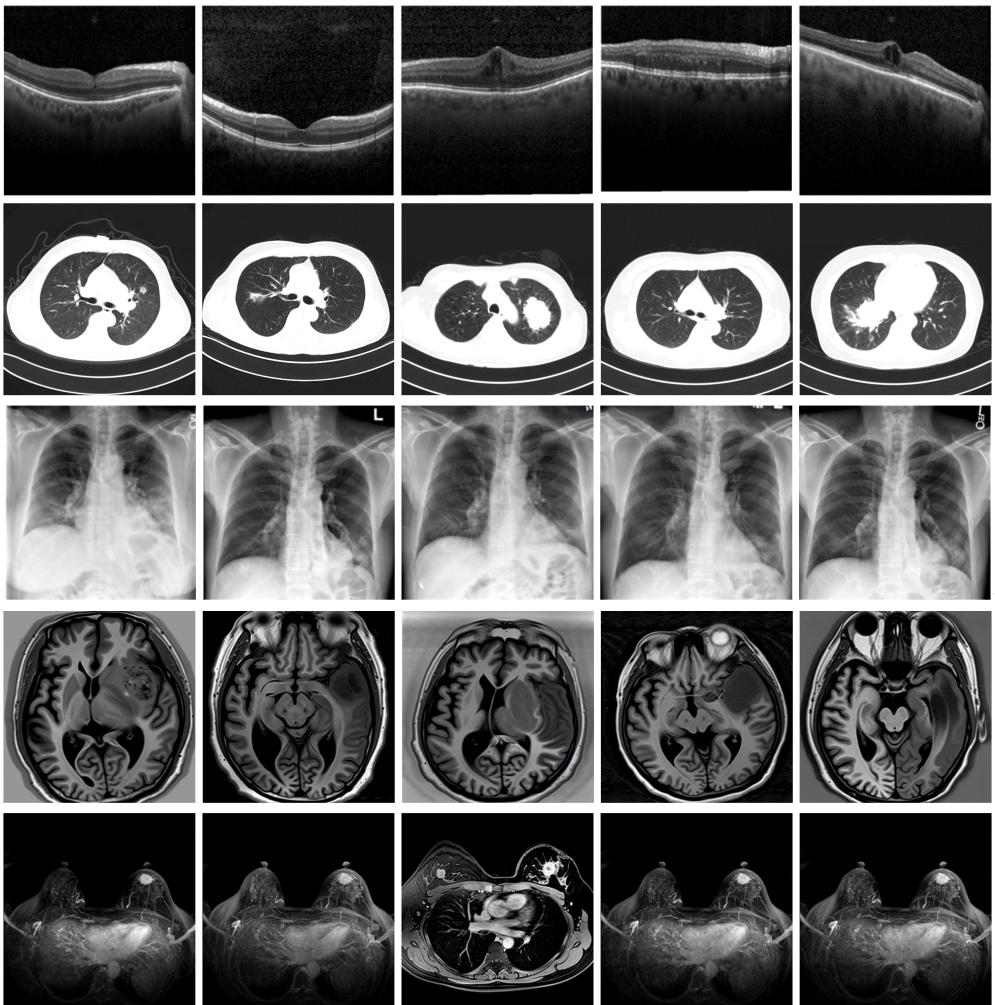

圖為由MINIM生成的高質量醫(yī)學合成圖像(受訪者供圖)

“目前公開的醫(yī)學影像數據非常有限,我們建立的生成式模型有望解決訓練數據不夠的問題?!北本┐髮W未來技術學院助理研究員王勁卓說,研究團隊利用多種器官在CT、X光、磁共振等不同成像方式下的高質量影像文本配對數據進行訓練,最終生成海量的醫(yī)學合成影像,其在圖像特征、細節(jié)呈現等多方面都與真實醫(yī)學圖像高度一致。

實驗結果顯示,MINIM生成的合成數據在醫(yī)生主觀評測指標和多項客觀檢驗標準方面達國際領先水平,在臨床應用中具有重要參考價值。在真實數據基礎上,使用20倍合成數據在眼科、胸科、腦科和乳腺科的多個醫(yī)學任務準確率平均可提升12%至17%。